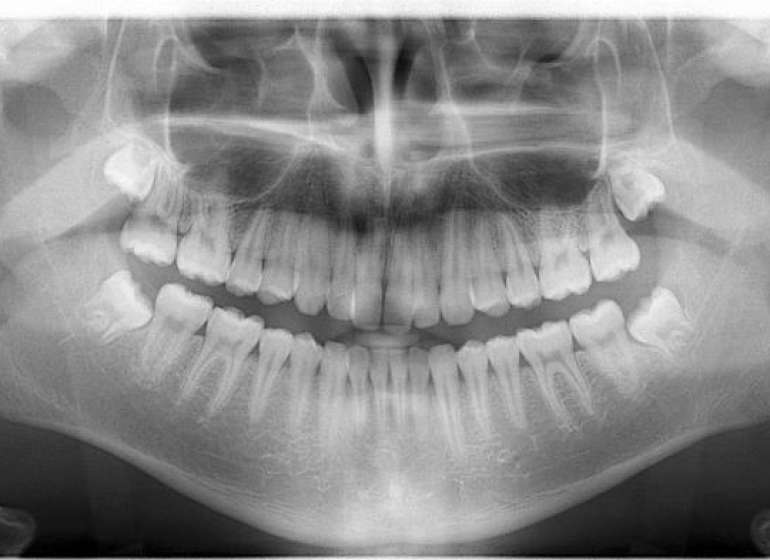

Panoram rentgen bütün dişlərin, alt və üst çənənin şəkli, buradakı patologiyaların tək bir şəkildə görülməsini təmin edən üsuldur.

- Panoram rentgen müalicənin planlaşdırmasının aparılmasına kömək edir.

- Panoram rentgenə çənə və dişlərdə gözlə görünməyən kista və şiş kimi törəmələrin diaqnostikasında ehtiyac duyulur.

- Çənə və dişlərlə bağlı cərrahi müdaxilələrdən öncə bu üsuldan mütləq istifadə olunmalıdır. Çünki bu rentgenlər müalicə aparılacaq sahəni geniş bir şəkildə göstərir.

- Bütün dişlərin görüntüsü tək bir rentgen şəklində görülə bilir.